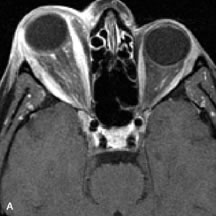

Muscle Disorders

Extraocular muscle enlargement in patients with thyroid-associated orbitopathy is demonstrated equally well with CT and MRI studies. However, the superior tissue contrast on MR images reveals better details of the relationships of the optic nerve to the thickened muscles at the orbital apex (Fig. 16).50 In addition, MRI may be able to differentiate between muscles that are enlarged as a result of edema and active inflammation and those enlarged because of fibrosis by their T2 relaxation times.21 Quantitative MRI was not found to be accurate in predicting the success of low-dose orbital irradiation.51 However, a muscular index relating the diameters of the rectus muscles to the bony orbital dimensions was useful in predicting optic nerve compression.52

Fig. 16. A-C, T1-weighted MR scans obtained with a high-resolution surface coil demonstrate fusiform enlargement of the extraocular muscles. The medial, lateral, and inferior rectus muscles are especially involved. Note the relative sparing of the tendinous insertions, a finding characteristic of this disease process, as well as fatty infiltration of the lateral and inferior rectus muscles. There is marked proptosis, best visualized on the sagittal image (A), and mild crowding of the optic nerve at the orbital apex.